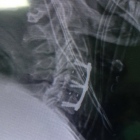

Hola, la mielomalacia es el sufrimiento medular que provoca degeneración progresiva debido a la falta de aporte sanguíneo, en el caso de la mielomalacia cervical la causa mas común es la enfermedad degenerativa... Ver más